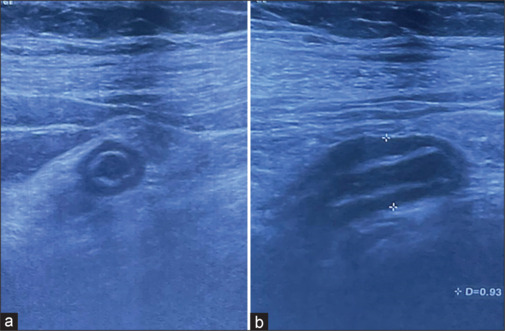

The interpretation of F-18 fluorodeoxyglucose positron emission tomography/computed tomography (FDG-PET/CT) scans can be confounded by incidental findings, as illustrated in this case of a 47-year-old woman with a history of breast carcinoma. Following neoadjuvant chemotherapy and mastectomy, she underwent FDG PET/CT for disease evaluation, revealing unexpected hypermetabolic activity in the right iliac fossa corresponding to acute appendicitis. Thus, FDG PET/CT has the potential to uncover treatable conditions beyond cancer and imaging findings need clinical correlation.

对F-18氟脱氧葡萄糖正电子发射断层扫描/计算机断层扫描(FDG-PET/CT)的解释可能会因偶然发现而混淆,正如本病例中一位47岁的乳腺癌病史女性所示。在新辅助化疗和乳房切除术后,她接受了FDG PET/CT进行疾病评估,发现右侧髂窝意外出现急性阑尾炎的高代谢活动。因此,FDG PET/CT有潜力发现癌症以外的可治疗疾病,影像学结果需要临床相关性。